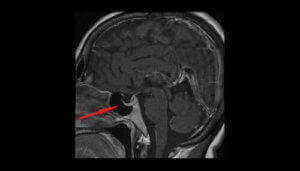

وأكثر الفحوصات التي تساعد على تأكيد التشخيص هي الأشعة المقطعية والتصوير بالرنين المغناطيسي.